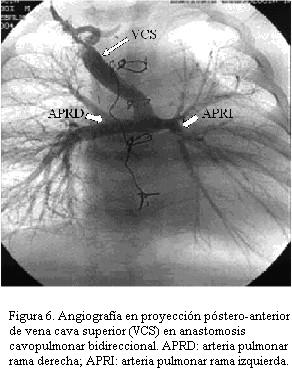

La evolución después del primer estadio sigue siendo grave a la espera de la corrección fisiológica que es el bypass parcial del ventrículo derecho (Glenn bidireccional) que comprende la anastomosis entre la vena cava superior derecha o eventualmente izquierda y la rama correspondiente de la arteria pulmonar (figuras 5 y 6) y aun antes de completar la cirugía de Fontan que implica la tunelización desde la vena cava inferior hasta la arteria pulmonar sea por vía intra o extraauricular.

A los 7 meses se realiza cirugía de Glenn (anastomosis cavopulmonar bidireccional o bypass parcial del ventrículo derecho).